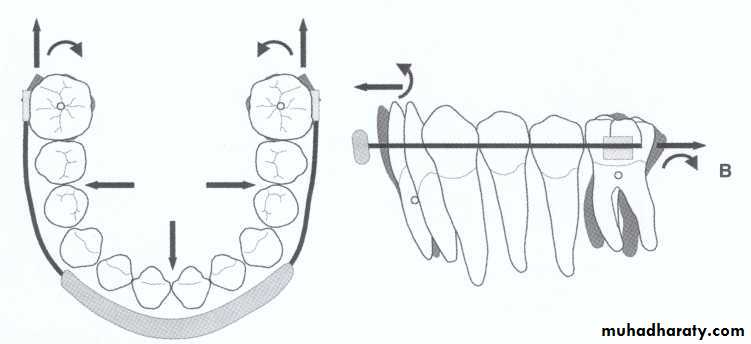

A- Reduction in size of primary canine.B- Expansion of arch, by tipping the molars distally and incisors slightly foreword while widening the arch in premolar area.

C- Extraction of primary canine but this create a possibility that permanent incisor will tip lingually reducing arch length, a conservative approach to place a lingual arch in canine extraction.

A- Expantion either use functional appliance (Frankle appliance, lip bumber, buccal shield ) or with fixed appliance.Note: lip bumber action is distalization of molars and proclination of incisors.